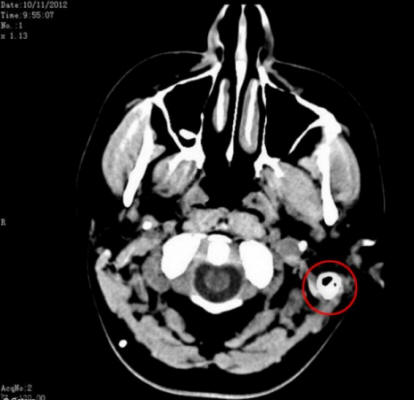

Ale poté, co našli způsob, jak odstranit přebytečnou tekutinu její mozek do břicha, její život se změnil. Drain, také známý jako gastroperitoneální zkrat, propojující mozek a žaludek, což mu umožňuje tráví mozkovou tekutinu a snižuje tlak na mozek.

Sam byl odkazován na řadu profesionálů, kteří měli podezření, že by mohla mít nádor na mozku. Naštěstí poté při provádění řady testů byl mozkový nádor vyloučen seznam možných příčin onemocnění. Doktoři však nebyli schopni určit, co se jí stalo. Odborníci zjistili pravdu příčina jejích zdravotních problémů až po bederní proražení.

Lidský mozek je obklopen tekutinou, která ho chrání od nárazu na lebku, ale Samovo tělo se ukázalo být vytváří tuto tekutinu třikrát více, než je norma. I poté diagnostikovat a brát 17 různých drog denně, Sam i nadále trpěl strašnými bolestmi hlavy.